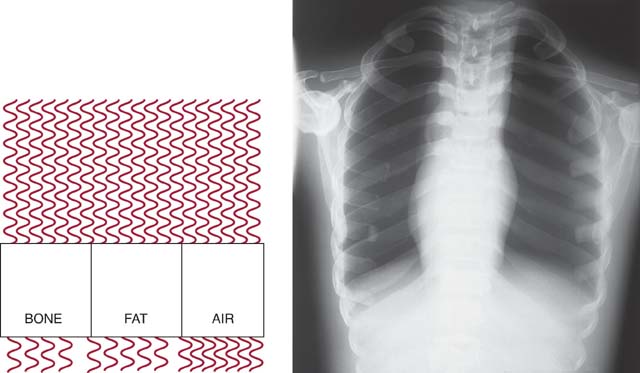

The amount of radiographic contrast achieved is also influenced by the composition of the anatomic part to be radiographed. As mentioned in Chapter 3, subject contrast is a category of radiographic contrast. The thickness of the tissue, effective atomic number, and cell compactness (tissue density) affect its absorption characteristics. The absorption characteristics of the anatomic tissue create the brightness levels produced on a radiographic image. Tissues that have a higher effective atomic number absorb more radiation than tissues with a lower effective atomic number.

Anatomic structures having a wide range of tissue compositions, varying in parameters such as effective atomic number and tissue density, demonstrate high subject contrast (Fig. 6-24). Anatomic structures consisting of a similar type of tissue demonstrate low subject contrast (Fig. 6-25). The radiographer cannot control the composition of the anatomic part to be radiographed. Changing the kVp alters its absorption and transmission within anatomic tissues. Knowledge about the absorption characteristics of anatomic tissues and the effect of kVp helps the radiographer produce a desired level of radiographic contrast.

FIG. 6-24 Higher subject contrast resulting from great differences in radiation absorption between tissues that vary greatly in composition.

FIG. 6-25 Lower subject contrast resulting from fewer differences in radiation absorption between tissues that are more similarly composed.